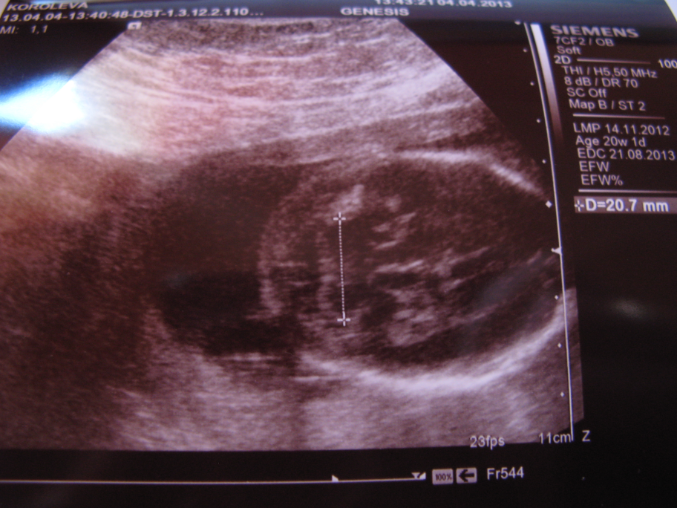

Наш экватор мы провели в Питере у родителей, поэтому отчет пишу чуть попозже:) Там же в питере съездили на 4D УЗИ:) остались очень довольны клиникой и врачами. Правда 4D почти нам не показали, малыш прятался так что сделали 2D и несколько раз включали 4D, но на диск записывать не стали, скромный у нас мальчик:)Доктор все подробно показала и рассказала, подробно осмотрели сердечко и мозг. Сказали что все у нас отлично! Малыш будет крупный:) на момент УЗИ нам было 20нед. 1дн., вес 362 гр. обхват головы - 182 мм, обхват животика - 150 мм., частота сердцебиения 146 уд. Отклонений не выявлено, вод в норма, вот только поставили что плацента низковато, но сказали вроде ничего страшного, я пока не читала по этому поводу ничего.

Это наша попа и ножка:) большего родителям решили не показывать:)

Это наши замечательные пяточки, бегающие по монитору, доктор только датчиком поймает а они топ топ по экрану, это было очень забавно

А это наша головушка вернее затылок:)